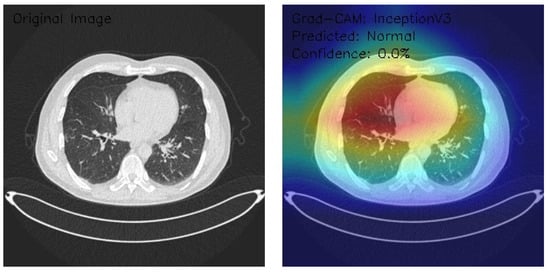

Analysis of InceptionV3 Model Performance on Lung CT Images with Grad-CAM Visualization

The results section of this study presents the detailed findings from an advanced analysis of three axial chest CT images processed using the InceptionV3 deep learning model. This analysis leverages the sophisticated capabilities of Grad-CAM to provide a comprehensive visualization of the regions within the CT images that the model identifies as significant for its predictions. Combining the robust classification performance of the InceptionV3 architecture with the interpretability offered by Grad-CAM, this approach not only evaluates the model’s predictive accuracy but also elucidates the spatial patterns of attention within the medical imaging context. This dual focus allows for a deeper understanding of the diagnostic potential of deep learning in radiology and the interpretive transparency essential for clinical application. The following results detail these observations, highlighting key insights into the model’s behavior and implications for automated diagnostic processes.

Figure 9 shows that the CT image reveals clear lung fields with well-defined bronchial structures, indicating no abnormalities in the original scan. The Grad-CAM visualization highlights a distinctive rainbow-like activation pattern, predominantly focusing on the central and bilateral lung fields with symmetric intensity. Despite these detailed attention patterns, the model classifies the image as Normal with a confidence score of 0.0%, pointing to significant issues in confidence calibration. This suggests the model can identify relevant anatomical regions but lacks reliability in translating these insights into confident and actionable classifications. Further calibration and optimization are necessary for clinical applicability.

Figure 9.

Grad-CAM visualization using InceptionV3 for lung CT scan with normal prediction. (Source: author’s analysis from data, 2024).

Figure 10 shows that the CT image analysis highlights scattered nodular opacities, suggesting potential abnormalities. The Grad-CAM visualization indicates peripheral activation patterns, with a notable focus on lateral lung regions. The heatmap’s color gradients suggest varying feature importance across these areas. Despite identifying relevant features, the model classifies the image as Malignant with a confidence score of 0.0%, reflecting significant uncertainty. This indicates a disconnect between the model’s feature detection and its confidence in classification, emphasizing the need for recalibration and potential retraining to enhance diagnostic reliability and decision-making accuracy.

Figure 10.

Grad-CAM visualization with InceptionV3 for lung CT image analysis reveals scattered nodular opacities, indicating possible abnormalities. (Source: author’s analysis from data, 2024).

Figure 11 shows that the CT image displays interstitial patterns, indicative of potential structural abnormalities. The Grad-CAM visualization highlights strong activation centrally and in the right lung, with an asymmetric attention distribution favoring the right hemithorax. Despite this focused feature analysis, the model classifies the image as Normal with a confidence score of 0.0%, suggesting significant limitations in the model’s confidence calibration and decision-making reliability. The mismatch between observed features and classification confidence underscores the need for model refinement, particularly in aligning activation insights with robust, actionable predictions.

Figure 11.

Grad-CAM visualization using InceptionV3 for lung CT scan with malignant prediction. (Source: author’s analysis from data, 2024).

This analysis evaluates three axial chest CT images processed by an InceptionV3 model with Grad-CAM visualizations, focusing on attention regions and classification outcomes. Image 1 shows clear lung fields with symmetric central activation, classified as Normal with 0.0% confidence. Image 2, with scattered nodular opacities, displays peripheral activation patterns and is classified as Malignant, again with 0.0% confidence. Image 3 exhibits interstitial patterns with strong central and right-sided activation, also classified as Normal with 0.0% confidence. The Grad-CAM visualizations highlight relevant anatomical features, but the model’s uniform low confidence scores reveal calibration and classification inefficiencies. Recommendations include the recalibration of confidence scoring, fine-tuning classification layers, and integrating ensemble methods. While feature detection appears robust, these refinements are critical for clinical reliability and decision-making.